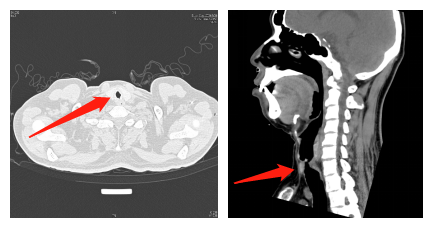

患者入院胸部CT显示患者气管上段明显狭窄,如箭头所示

支气管镜显示声门下气管狭窄处直径仅为5毫米左右。“严重复杂的气管狭窄治疗非常困难,需全面运用多种支气管镜介入治疗技术和手段,帮助他耐受长时间手术的气管插管麻醉。”牟向东说。结合患者的实际情况,牟向东决定用电子支气管镜球囊扩张及电烧冷冻治疗为他扩张气道。